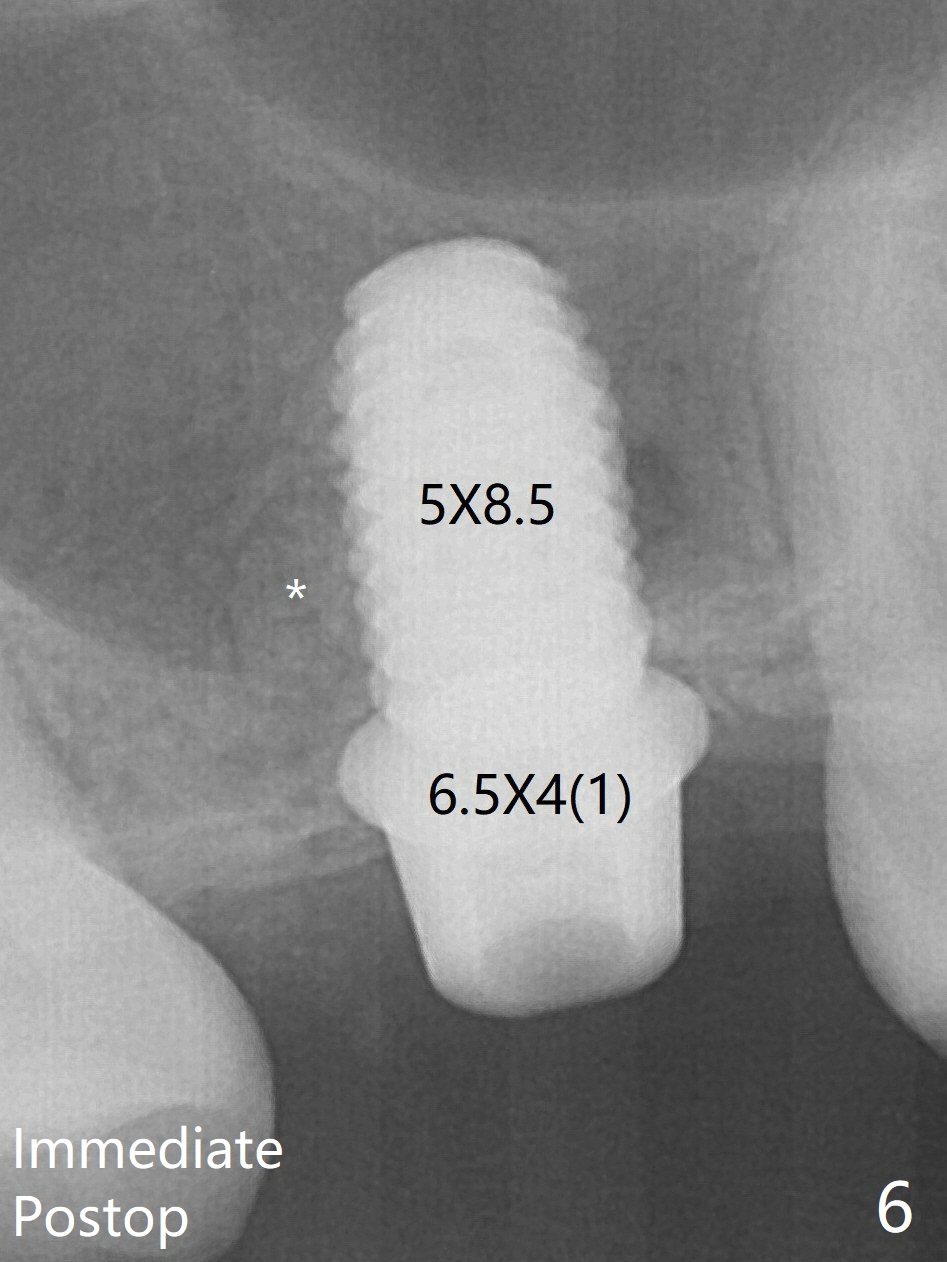

A 4.5x10 mm dummy implant is placed with high torque after 4x7.3 mm drill with 3 mm stopper so that 4.5x7.3 mm drill with 1 mm stopper is used before placement of a 5x8.5 mm final implant with ~ 35 Ncm (Fig.6-7). There is no pain when a 5.2x4(2) mm cemented abutment is torqued at 30-35 Ncm before impression (Fig.8). *: bone graft in the sinus.